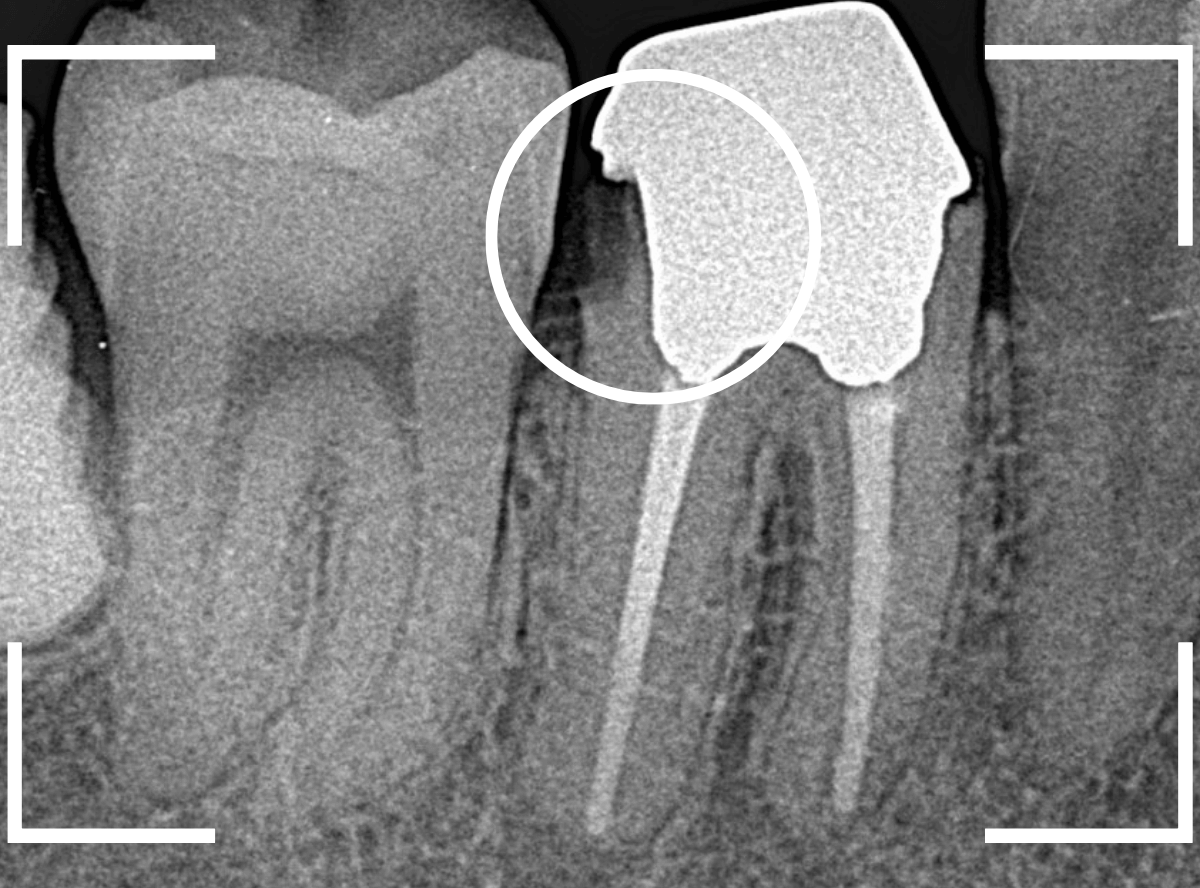

レントゲン写真で確認すると、歯の奥側が虫歯になり始めています。

虫歯のすき間に物がつまりやすくなり、歯肉の状態がイマイチだったのかもしれません。

この虫歯を除去しないままさし歯をお作りしても、よい治療にはなりません。

短期間で外れて再治療になる可能性も高いですので、まずは虫歯の再治療をします。